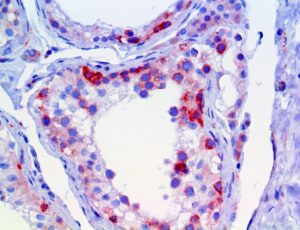

The first cytokines released are interleukin 1β (IL-1β) and tumor necrosis factor-α (TNF-α), which attract a variety of circulating white blood cells (WBCs) to the infection site, including neutrophils, monocytes, macrophages, and natural killer (NK) cells. This response, along with the antipathogenic chemicals released by these cells (i.e., complement), comprise the innate immune response. These cells directly attack the invading pathogen and also release additional cytokines, chief among them interleukin-1 and 6 (IL-6). IL-6 is essential for invoking the adaptive immune response, which calls T-cells, B-cells, and T helper (Th) cells to the infection site. IL-6 also stimulates further recruitment, proliferation and activation of macrophages.

This activation induces inflammatory monocytes to highly express IL-6, starting a localized and then systemic cascade effect that results in hyperproduction of IL-6, which accelerates the inflammatory process. Because IL-6 also increases vascular permeability, excessive levels cause blood vessels to become very leaky. This, along with clotting factors released from vascular endothelial cells, stimulates the coagulation cascade, resulting in microthrombosis (tiny clots), which leads to ischemia and tissue death of the kidney, intestines, heart, liver, brain and extremities.